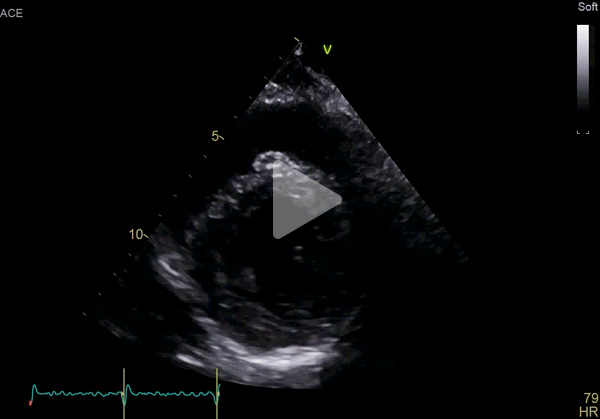

ETT :

- Hypertrophie ventriculaire gauche à prédominance septale (SIVd 12 mm, PPVG 12 mm) sans obstruction de repos, de fonction systolique conservée à 60 % en Simpson biplan. Cinétique homogène, SLG altéré à - 16 % en cocarde

- Profil mitral restrictif

- VD fin de bonne fonction longitudinale

- Pas de dilatation du massif atrial

- Pas de valvulopathie mitroaortique significative. Aorte ascendante non dilatée

- Veine cave inférieure fine respirante. Péricarde sec

Vidéo 3 : 4 cavités